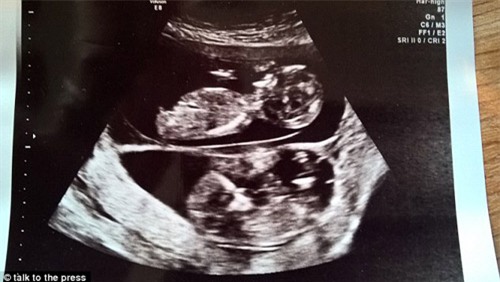

Hình ảnh siêu âm thai khi các bé được 12 tuần.

Sau đó một tuần, chị Susie đi siêu âm thì biết mình mang thai đôi. Và đến tuần thứ 12 của thai kỳ thì bác sĩ phát hiện một em bé của chị nhỏ hơn rất nhiều so với bé kia và cho rằng hai bé được thụ thai cách nhau hơn một tuần. Quá trình mang thai của chị Susie sau đó diễn ra khá suôn sẻ. Hai thai nhi đều phát triển tốt, mặc dù một trong hai bé luôn nhỏ hơn bé còn lại.